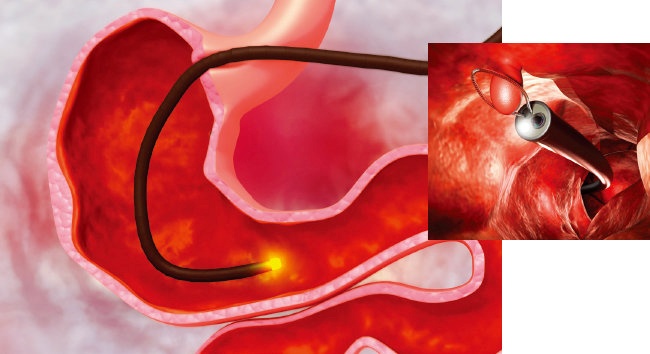

위궤양을 치료받으신 후에도 정기적으로 검진을 받는 것이 필수적입니다. 검진을 통해 궤양의 재발 여부를 체크하고, 적절한 조치를 취할 수 있습니다. 가장 흔히 시행되는 검사는 위내시경을 통한 검사입니다.

내시경을 통해 위의 상태를 직접 확인할 수 있으며, 필요한 경우 생검을 통해 추가적인 진단을 진행할 수 있습니다. 이러한 조치는 위장 질환의 초기 발견과 조기 대응에 중요한 역할을 합니다.